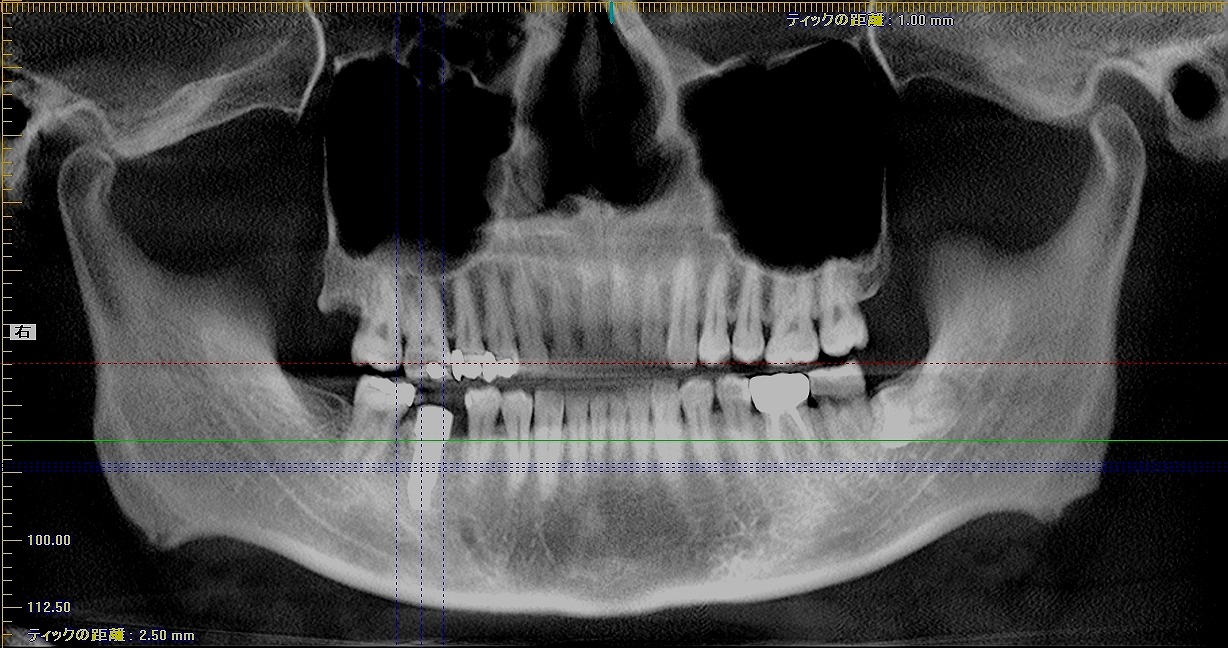

術前術後のパノラマになります

5mmの13mmというインプラントを埋入しています